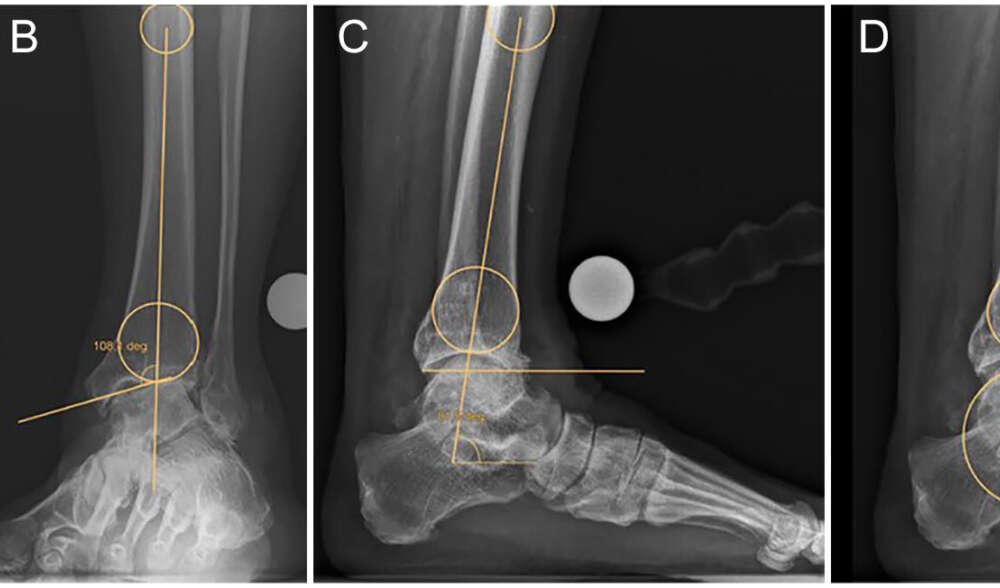

Die vorhandene Literatur zur Überlegenheit der patientenspezifischen Instrumentierung (PSI) bei der Knöchel-Totalendoprothese (TAA) gegenüber der Standardreferenzierung (SR) ist begrenzt. Als Vorteile werden unter anderem eine bessere Implantatausrichtung, kürzere Operationszeiten und eine höhere Genauigkeit bei der Vorhersage der Implantatgröße genannt. Ziel dieser retrospektiven Studie war es, die PSI in den Händen eines erfahrenen Fuß- und Sprunggelenkschirurgen zu analysieren, der sowohl mit der PSI als auch mit der SR für dieses spezielle Implantat noch nicht vertraut war, und zwar im Hinblick auf die Bestimmung der Implantatausrichtung, der Operationszeiten und des radiologischen Kurzzeitergebnisses sowie der Vorhersage der Implantatgröße für tibiale und talare Komponenten.